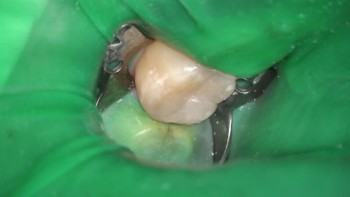

О стоматологе

Проводит лечение на эксклюзивном микроскопе Карла Цейса (Zeiss Extaro 300) с полным сопровождающим фотопротоколом. За счет многократного увеличения и оснащения микроскопа специальным светом, Татьяна Андреевна достигает совершенного подбора оттенков зуба при реставрациях, а также может диагностировать кариес на самых начальных стадиях, что невозможного сделать без микроскопа. Регулярно принимает участие в международных стоматологических форумах и конгрессах. Общительный и позитивный человек, а в работе – отличается тщательностью и аккуратностью. Ее профессиональное кредо – делать так, как хотела бы сделать для самой себя. С энтузиазмом увеличивает свой багаж профессиональных знаний и опыта. Стоматолог-терапевт. Общительный и позитивный человек, а в работе – отличается тщательностью и аккуратностью. Ее профессиональное кредо – делать так, как хотела бы сделать для самой себя. С энтузиазмом увеличивает свой багаж профессиональных знаний и опыта.

Бойцова Татьяна Андреевна: портфолио (3)